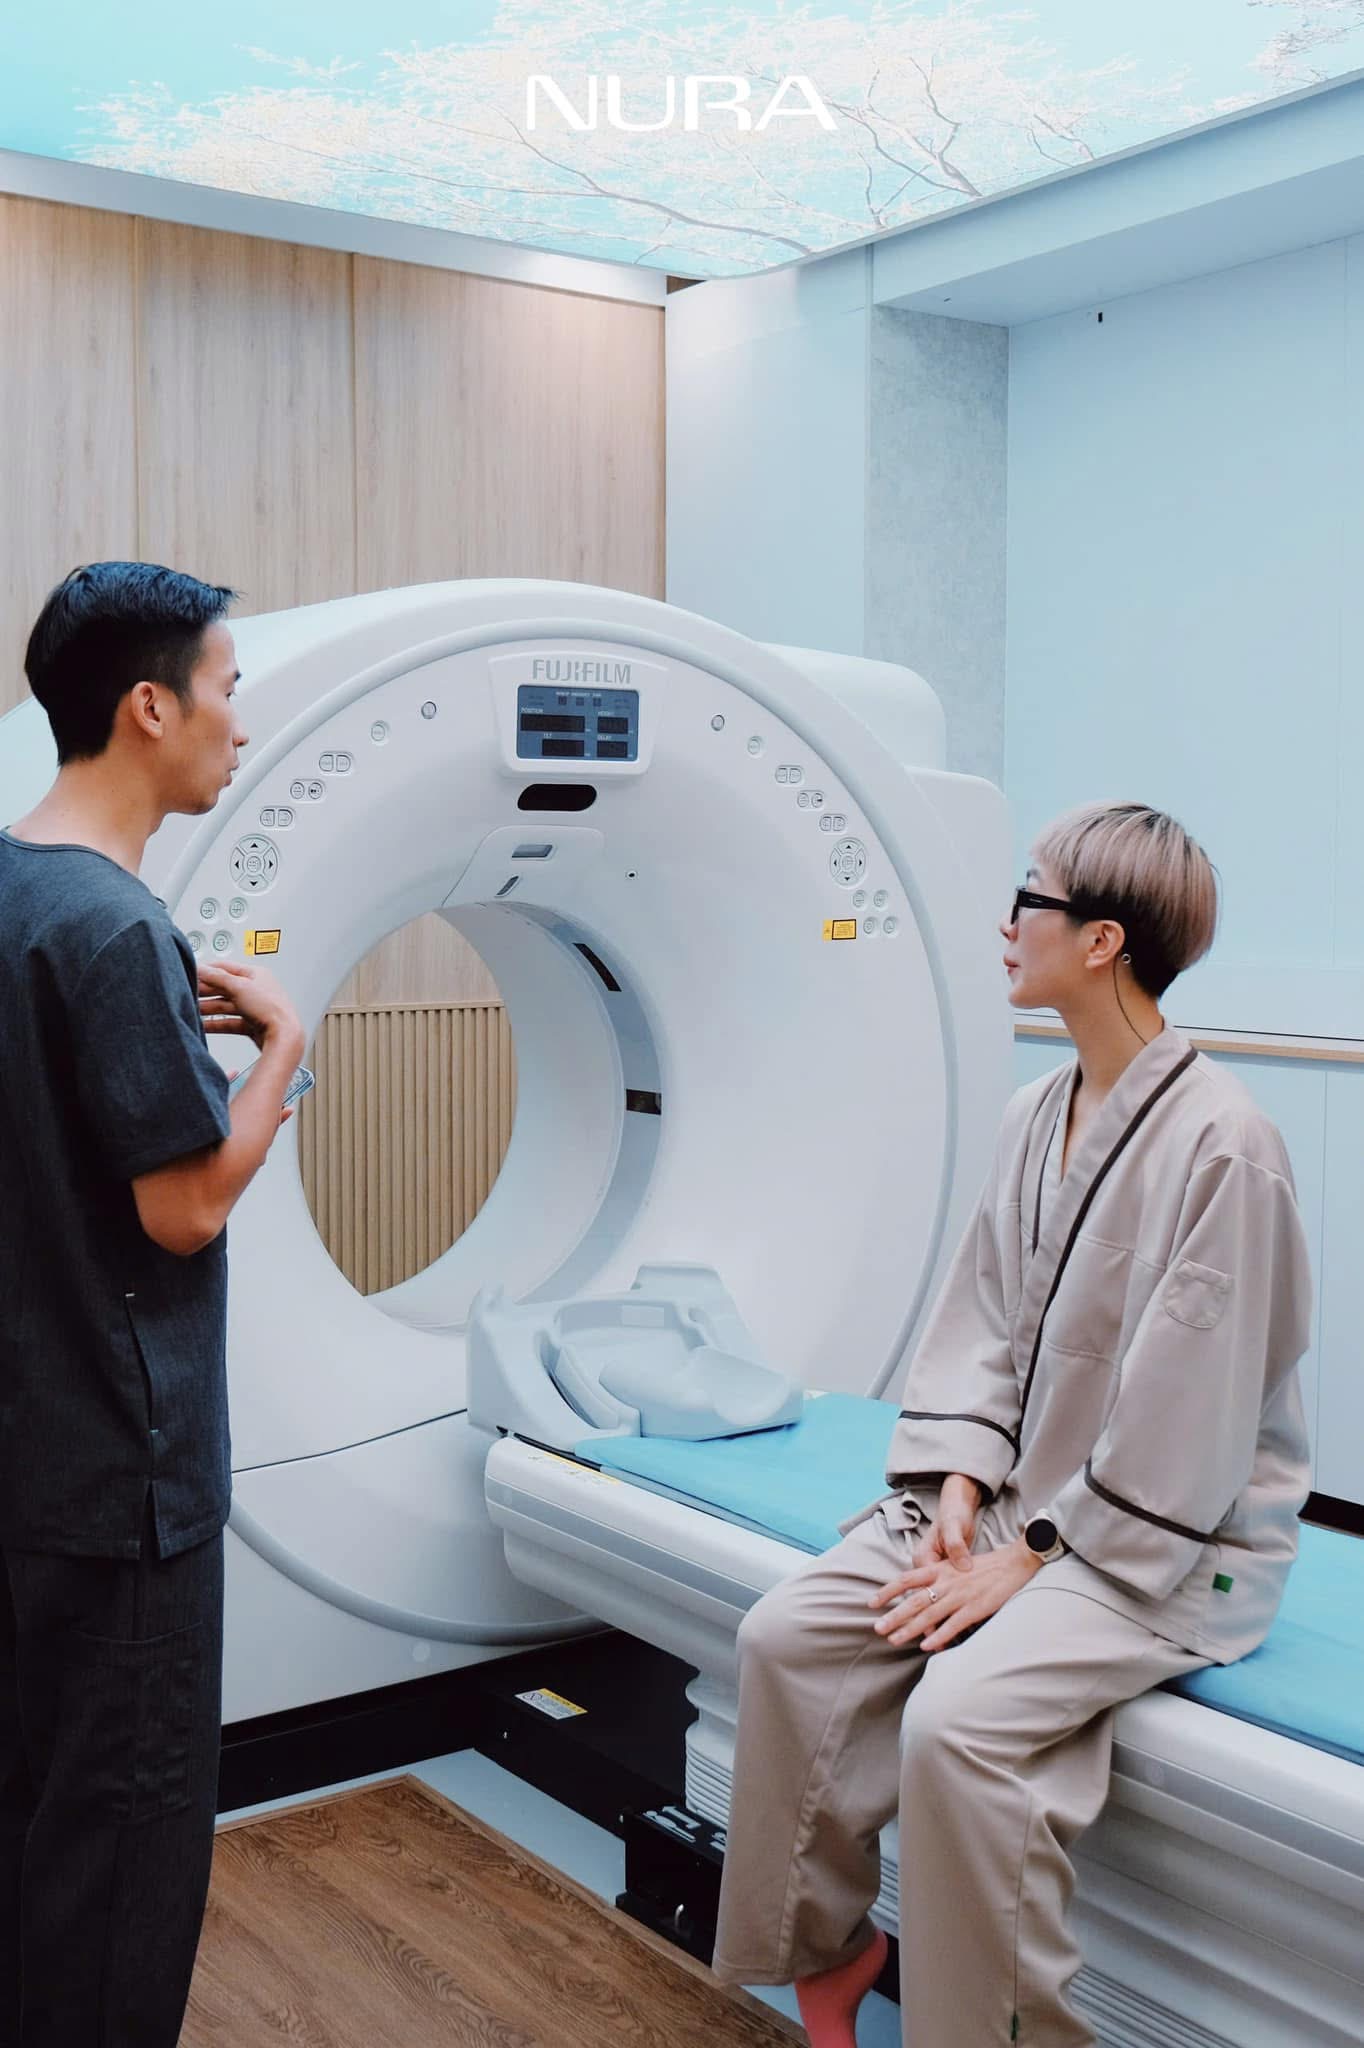

Máy chụp CT tại NURA được thiết kế để giúp quá trình tầm soát diễn ra thoải mái nhất có thể. Lỗ giàn máy của NURA (lỗ hổng mở trong máy CT – PV) lớn hơn các máy khác để giảm cảm giác sợ hãi và lo lắng của khách hàng. Đặc biệt, phòng chụp CT tại NURA được trang bị công nghệ tiên tiến nhất, đảm bảo không chỉ giúp chẩn đoán chính xác mà còn giảm thiểu tối đa bức xạ lên đến 97%, bảo vệ sức khỏe người bệnh. Bởi vậy, mọi người không cần phải tiêm thuốc cản quang trước khi chụp.

“Chúng tôi sử dụng công nghệ tái tạo 3D tiên tiến nhất, giúp mở rộng phạm vi bao phủ và tăng tốc độ quét, đảm bảo hiệu quả và độ chính xác cao trong từng hình ảnh. Máy chụp CT hoạt động với tốc độ cao, bạn sẽ chỉ cần nín thở trong khoảng 7–8 giây, lắng nghe và làm theo hướng dẫn phát ra từ hệ thống loa tự động”, BS. Nguyễn Hải Anh – Giám đốc chuyên môn của Nura cho biết.

Quy trình tại đây diễn ra nhanh chóng, gọn gàng và hoàn toàn nhẹ nhàng. Chỉ trong vòng khoảng 5 phút, cả hai lần chụp CT đã được hoàn tất mà không hề gây ra cảm giác khó chịu hay lo lắng.